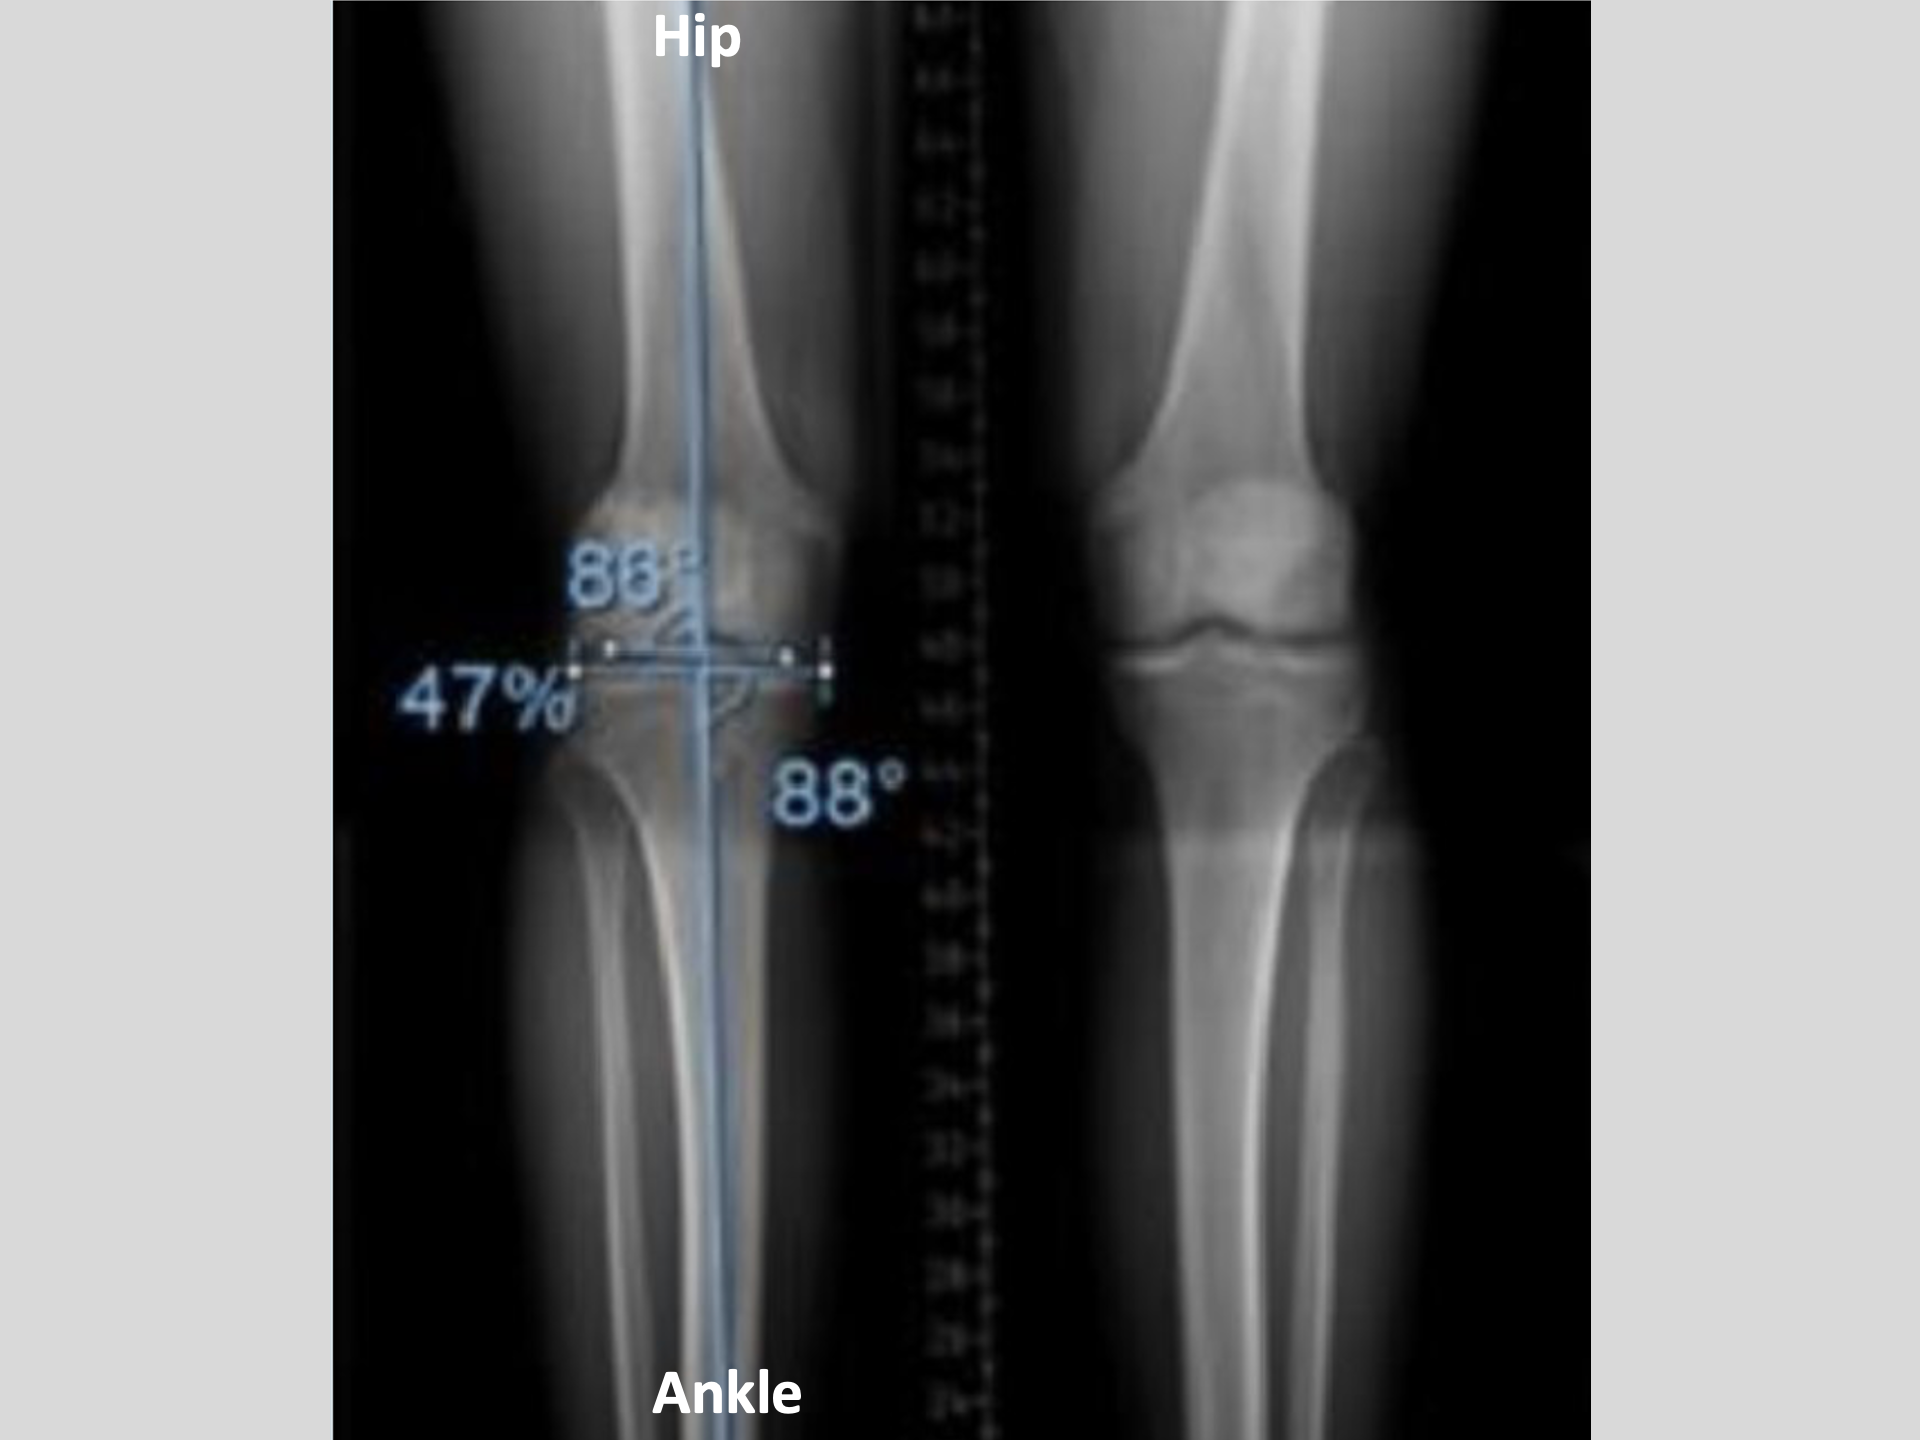

John's LEFT Knee

Let's take a look at John's x-ray film..